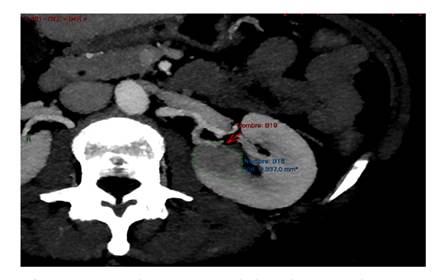

69-year-old woman with a history of IA endometrial cancer treated with adnexa-hysterectomy in March 2021. In a follow up CT scan a completely endophytic hypo-vascular tumor on the left kidney was evidenced, poorly delimited at the level of the upper polar line, approximately 30 mm in the axial plane, suggesting a papillary or chromophobe tumor. RENAL SCORE: 1+3+3+p+2=9p (Figure 1).

Figure 1 Retropyelic branch entering the tumor. Cross-section